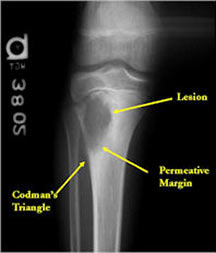

- Permeative lesion with indistinct border that is poorly marginated

- Osteolytic and expansile on X-ray with very little osteoid production

- May have Codman’s triangle and malignant appearing periosteal reaction in most cases

- Cortical destruction and soft tissue extension are common

- Expands contour of bone and may appear similar to an ABC (aneurysmal bone cyst)